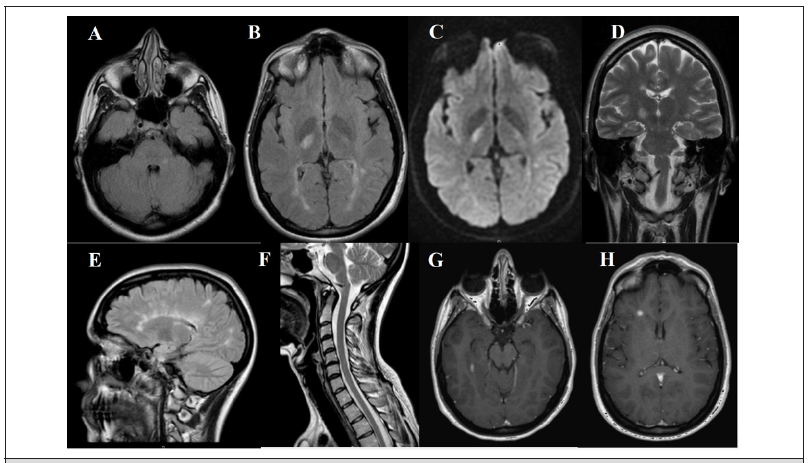

Laboratory workup, including complete blood count, renal and liver function tests, thyroid function, vitamins, calcium and phosphorus metabolism, folate and copper was normal. Brain Magnetic Resonance Imaging (MRI) without contrast, performed 3 months after the onset of symptoms, revealed multiple supratentorial and infratentorial white matter hyperintense T2 and Fluid Attenuated Inversion Recovery (FLAIR) lesions, being the largest in the right lateral thalamus, which showed mild restricted diffusion. Furthermore, after that initial MRI, a new cerebral and medullar MRI with contrast, that was performed 6 months after symptom onset, showed 2 new enhancing lesions in the right temporal subcortex and periventricular areas (Figure 1). Cerebrospinal fluid analysis showed oligoclonal bands. The 2017 Mc Donald diagnostic criteria for MS were fulfilled and a diagnosis of PDK as the initial manifestation of MS was made. She was treated with carbamazepine 100mg 2 times a day with complete resolution of the attacks.

Figure 1: MRI images at three months after onset (A-D): axial FLAIR images (A, B) with supratentorial and infratentorial white matter hyperintense lesions, being the largest in the right posterior thalamus, which shows mild restricted diffusion (C); coronal T2 image (D) with hyperintense right thalamic lesion. Six months after onset (E-H): coronal FLAIR (E), T2 medullar (F) and T1 contrast images show right temporal enhancing lesion (G) and right periventricular (187